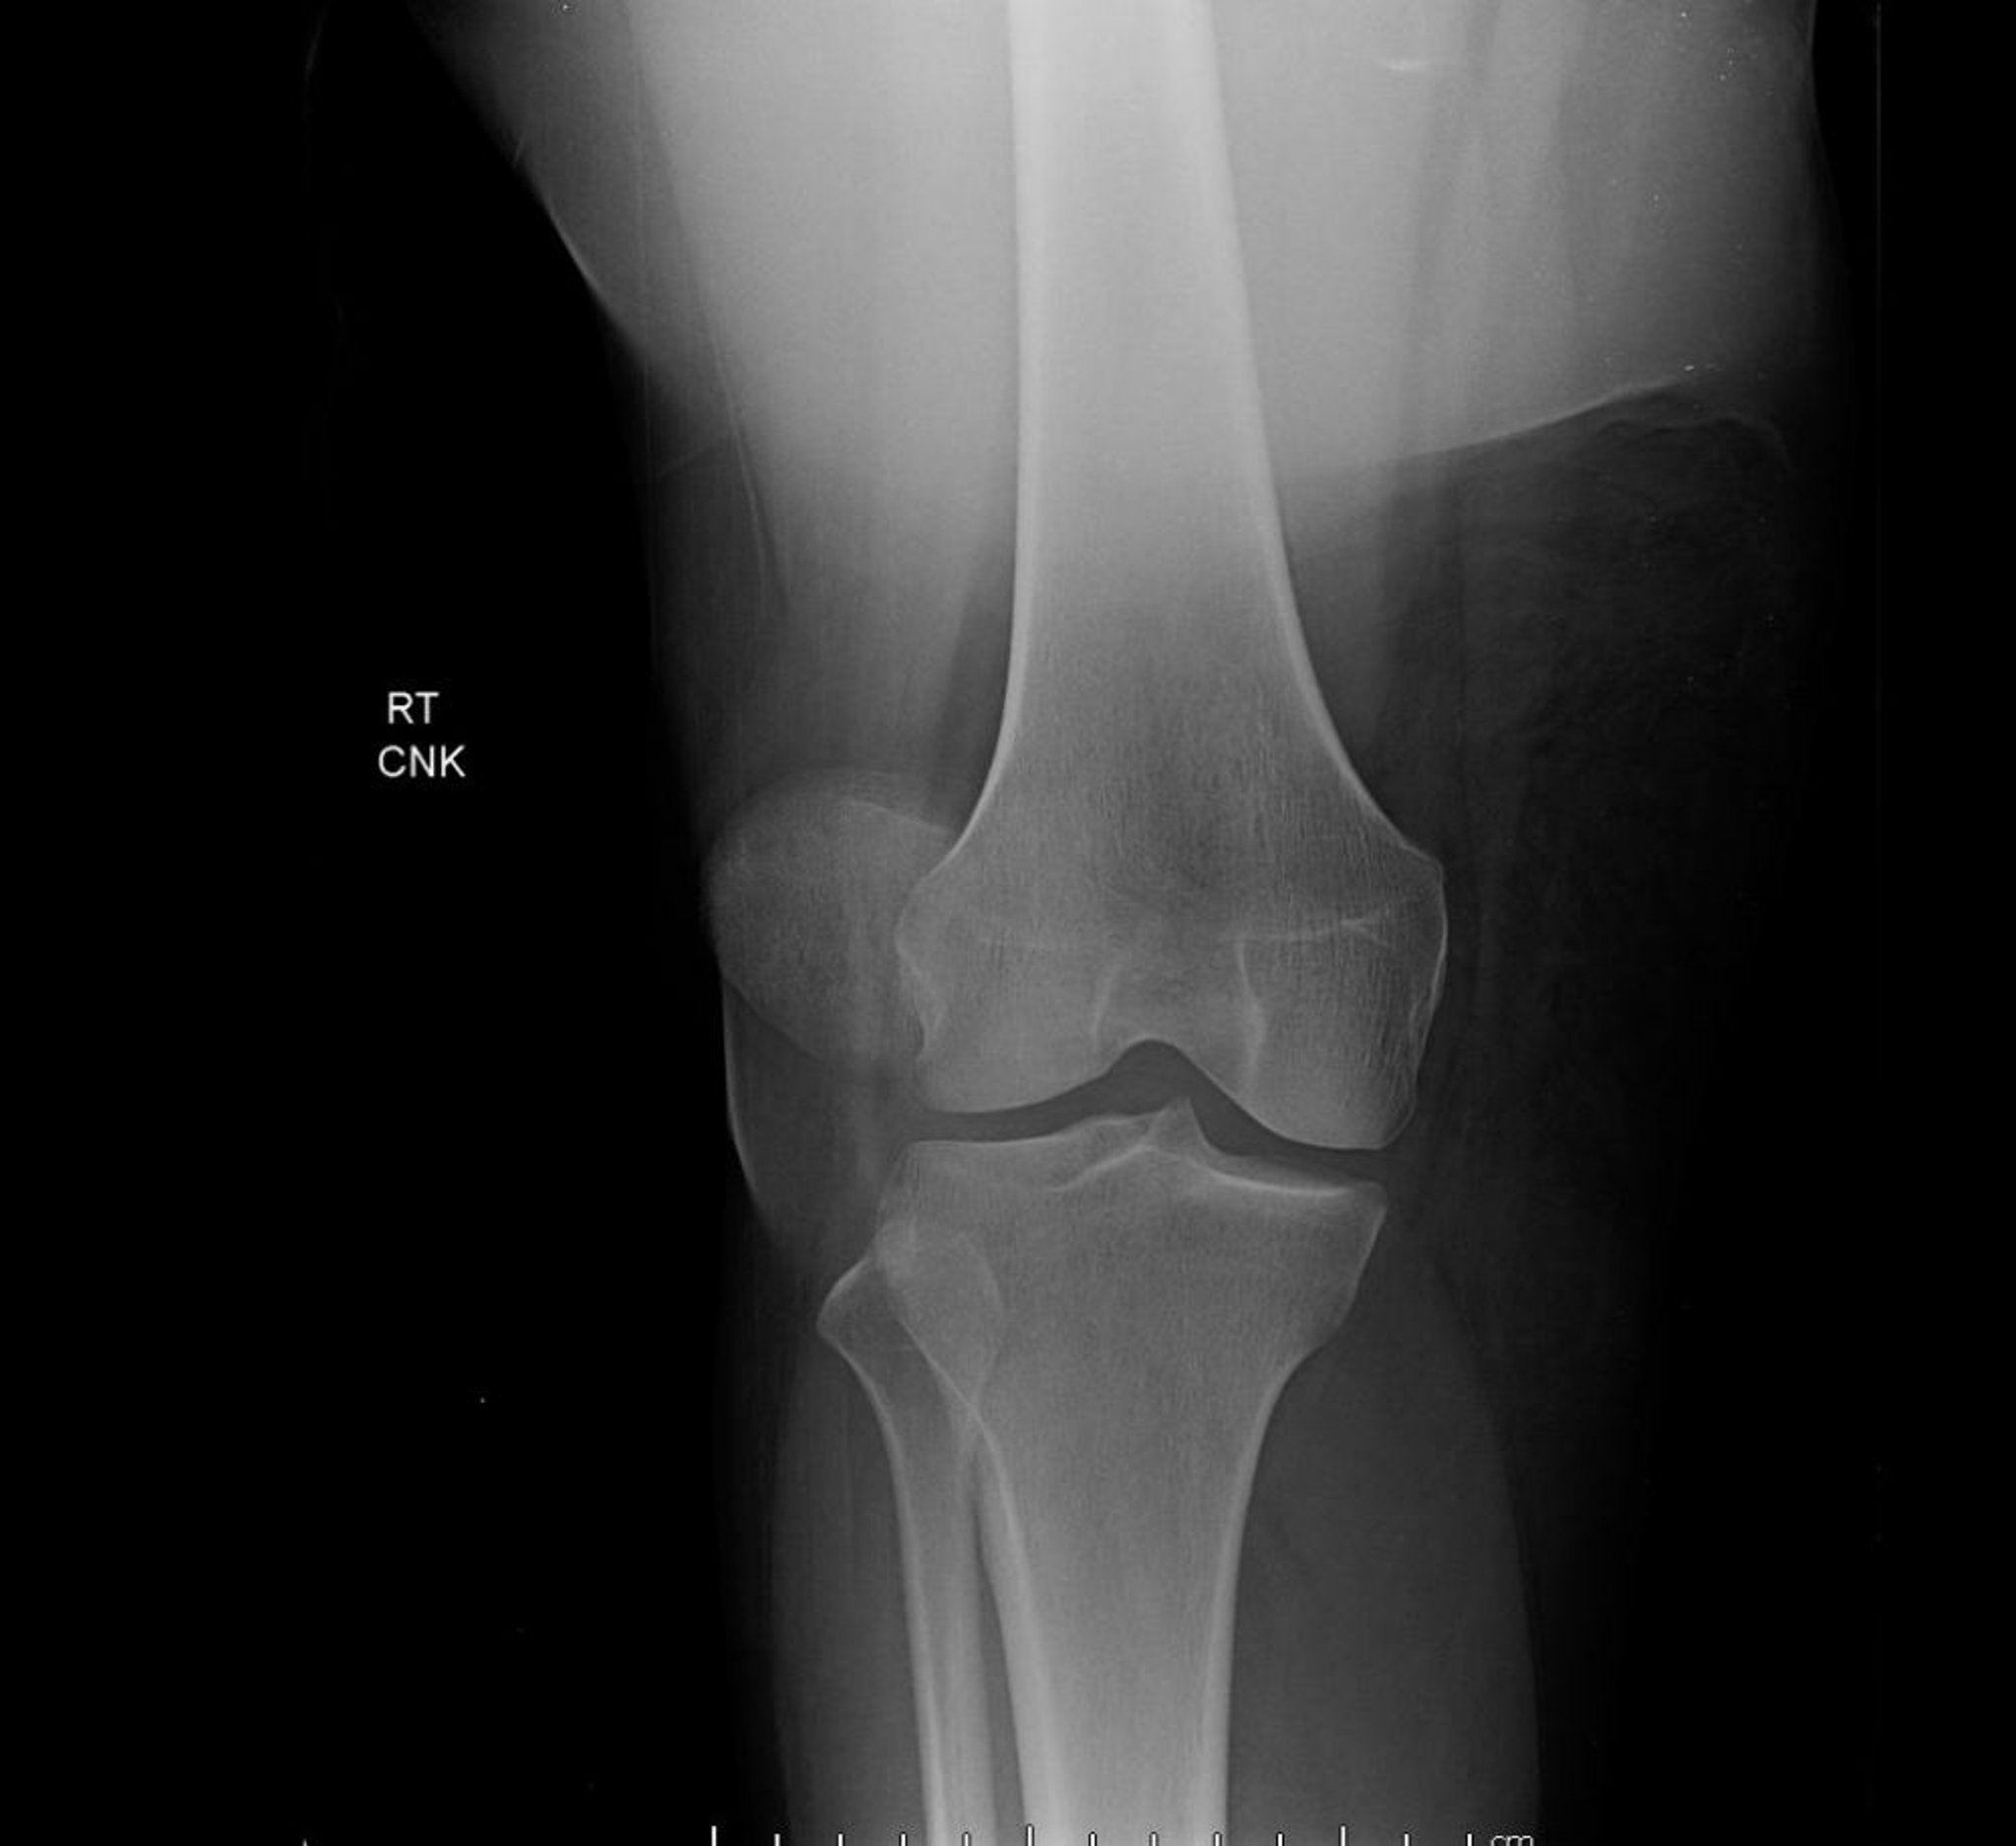

膝蓋骨脱臼(X線)

この膝関節の前後像は,大腿骨顆間の正常な位置から外れた膝蓋骨の極端な側方変位を特徴とする膝蓋骨脱臼を示している。

Image courtesy of Danielle Campagne, MD.